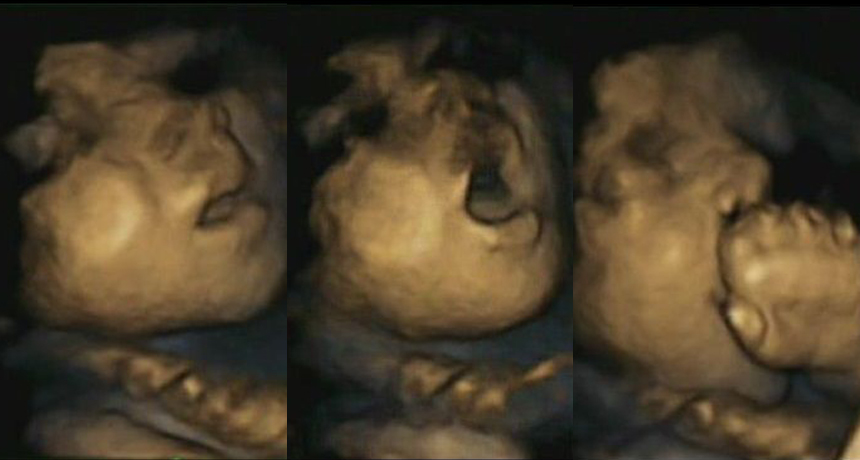

This 32-week-old fetus’ mouth opens in anticipation of a touch, a purposeful movement that may form the basis of feeding behavior later.

Nadja Reissland